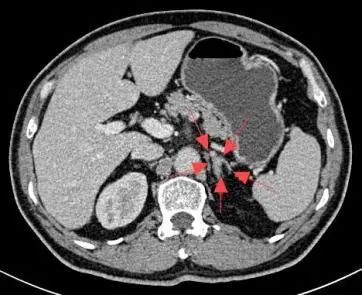

导管“寻路”:医生在X光引导下,通过血管造影精准导航,将导管送至肾上腺静脉,过程约30分钟。

58岁的杨先生患高血压多年,平日里血压控制不佳,近1年来出现血钾减低,间断进行补钾治疗后仍无法将血钾维持在正常范围。于是来到市四医院寻找原因,CT提示左侧肾上腺结节样增生,考虑杨先生存在原发性醛固酮增多症,为了明确双侧肾上腺的优势分泌侧来准确指导外科手术方案。医院介入室团队为患者进行了双侧肾上腺静脉采血术,血检结果提示左侧肾上腺为优势分泌侧。2周后,杨先生在泌尿外科接受了腹腔镜下左侧肾上腺切除术,术后血压恢复正常,无需药物辅助控制。